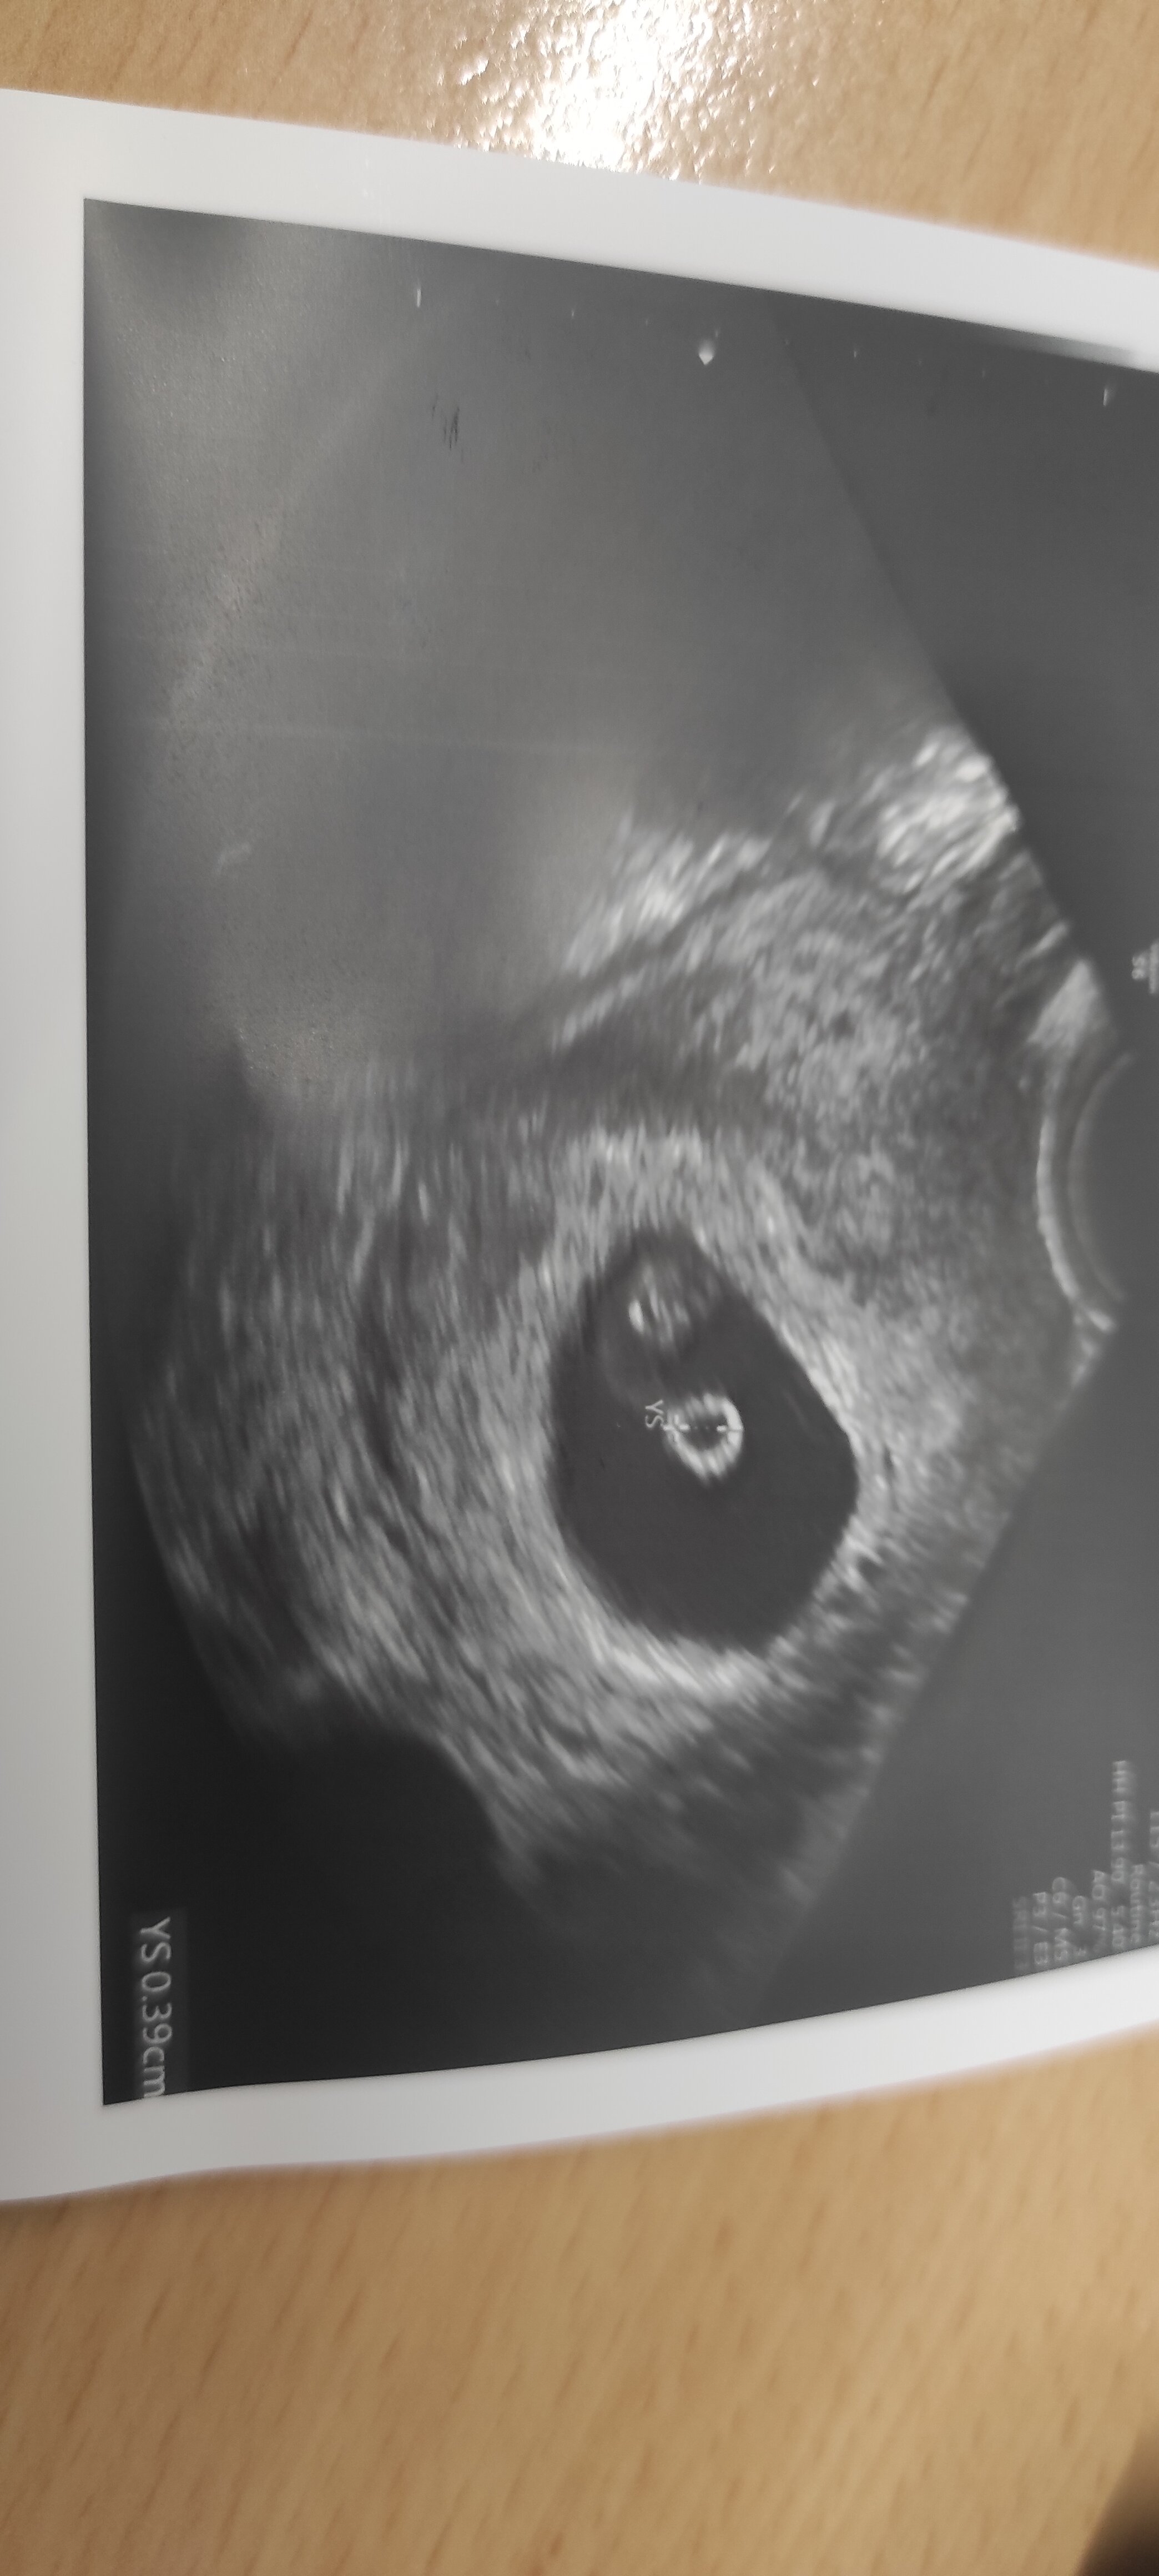

Hej 😁 ja już po wizycie ☺️ serduszko bije, póki co ciąża "żywa i zdrowa" 😁 dostałam całą listę badań do wykonania, USG piersi i parę innych rzeczy ☺️ idę też od razu na krzywą, w związku z insulinoopornością i cukrzycą w zeszłej ciąży.

Załączniki

• IMG_20220822_095244.jpg

IMG_20220822_095244.jpg

648,2 KB · Wyświetleń: 77